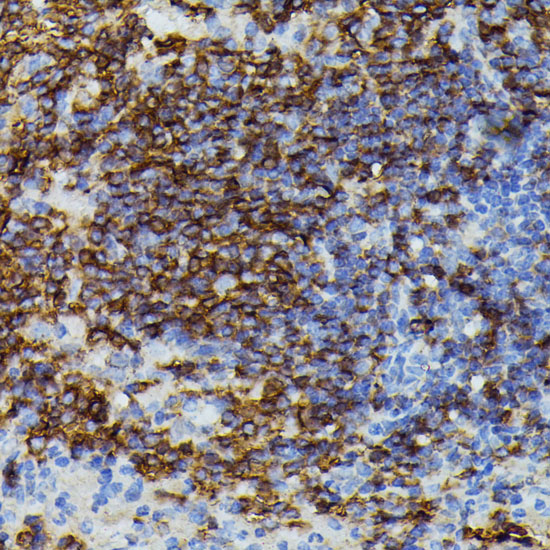

Immunohistochemistry of paraffin-embedded rat spleen using APOC3 at dilution of 1:100 (40x lens).

Immunohistochemistry of paraffin-embedded human liver using APOC3 at dilution of 1:100 (40x lens).

Immunohistochemistry of paraffin-embedded mouse spleen using APOC3 at dilution of 1:100 (40x lens).